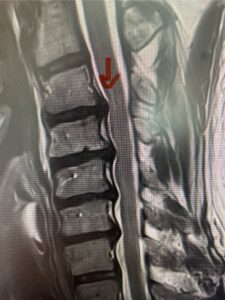

This 61-year-old female with a history of severe osteoporosis and a prior history of a laminectomy from l2-S1 with an L5-S1 instrumented fusion, presents with progressive low back pain and right lower extremity radiculopathy. MRI revealed a grade 1 L2-3 spondylolisthesis with severe stenosis mainly from severe right L2-3 facet joint hypertrophy which was compressing the right L3 descending nerve root. (Fig. 1). She had failed conservative management consisting of physical therapy and pain management with epidurals. She underwent an L1-3 revision laminectomy where we had to dissect a plane underneath the inferior aspect of the L2 lamina. We performed an instrumented fusion at L2-3 with special hydroxyapatite-coated screws to improve fixation to surrounding bone given here severe osteoporosis (Fig. 2) This worked out well and the patient had an uneventful recovery with relief of her leg pain.

Fig: 2a: AP and lateral intraoperative fluoroscopic images demonstrating good placement of L2-3 pedicle screws